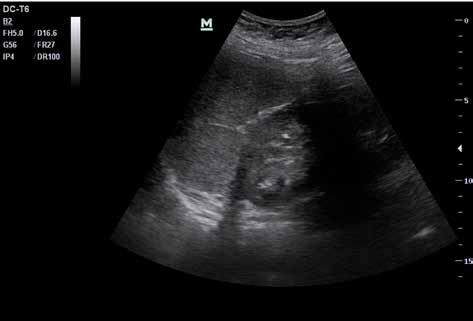

Abb. 37 ˘ Freie Flüssigkeit (FAF) (1) im Morison-Pouch. Rechtsseitiger Flankenschnitt Abb. 38 ˘ Freie Flüssigkeit (FAF) (1) im Koller-Pouch. Linksseitiger Flankenschnitt

Zunächst sammelt sich mögliche freie Flüssigkeit an drei typischen präformierten Stel len im Bauchraum und kann hier sonografisch dargestellt werden. Dies sind der MorisonPouch, der Koller-Pouch und der Douglas-Raum (von engl. „Pouch“ für „Beutel“, Abb. 34 –36).

Der Morison-Pouch ist eine Aussackung des Peritoneums zwischen Leberunterrand und rechter Niere. Dem entspricht auf der Gegenseite der Koller-Pouch zwischen Milz und linker Niere. Der Douglas-Raum befindet sich dorsal hinter der Harnblase und zieht bis ins kleine Becken.